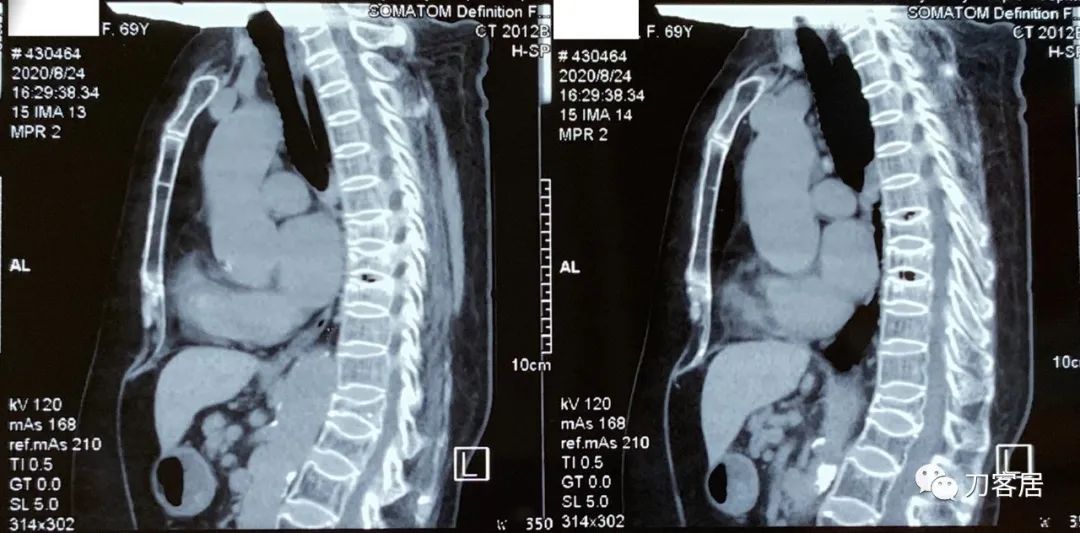

图07-20200824白银市人民医院胸椎CT

图08-20200824白银市人民医院腰椎CT